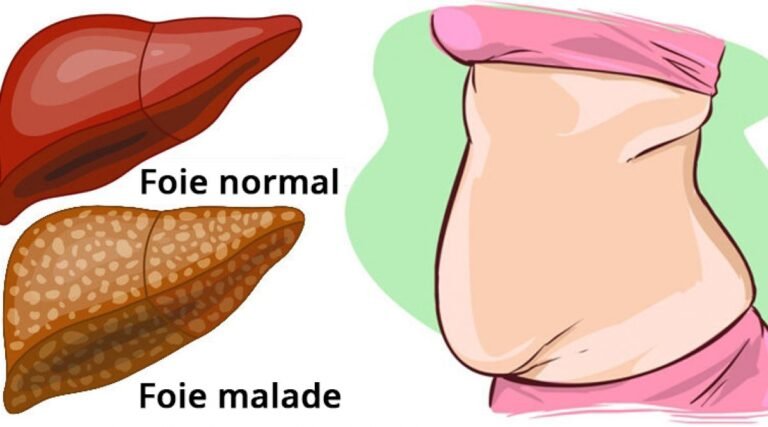

Notre mode de vie et nos habitudes alimentaires affectent notre santé, en particulier notre système digestif. En…